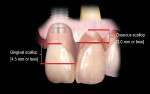

The real challenge when removing the two centrals is to evaluate what happens to the papilla between them following extraction.10,11 Before extraction the osseous crest around both centrals, assuming no periodontal disease exists, roughly follows the scalloped nature of the cemento-enamel junctions as they flow from the facial into the interproximal resulting in an average osseous scallop of 3 mm. Therefore the average interproximal bone height is 3 mm coronal to the facial crest of bone. Since the soft tissue typically follows the scallop of the bone, the osseous scallop results in a gingival scallop of 3 mm. However, when teeth are present an interesting phenomenon occurs. The gingiva on the facial of the tooth is positioned so that on average the free gingival margin is 3 mm coronal to the crest of bone. But as we saw earlier, the interproximal papilla between teeth is positioned on average 4.5 mm coronal to the interproximal crest of bone, 1.5 mm on average more coronal to the crest of bone than the facial tissue is. This additional 1.5 mm with the 3 mm average osseous scallop results in the tip of the papilla being an average 4.5 mm to 5 mm coronal to the facial free gingival margin (Figure 2).